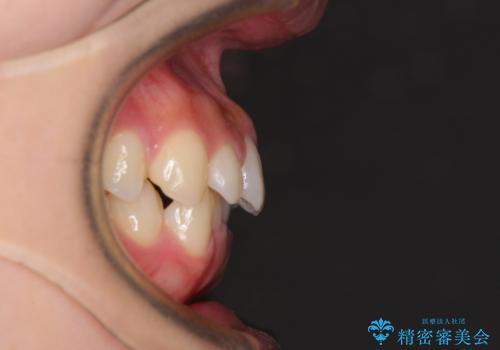

- 前歯のデコボコやクロスバイト、口元の突出感を気にして来院された患者様です。

上下左右の第一小臼歯4本を抜歯して、ワイヤー装置にて矯正治療を行うこととしました。

途中出産や育児があり、治療期間長くなってしまいましたが、ストレスなく唇が閉じられるような口元に仕上げることができました。